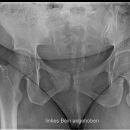

Becken tief a.-p.

Fraktur, Luxation, Z.n. Osteosynthesematerial

1. Wahl bei Frage Fraktur Hüfte/Luxation/TEP

Symmetrisch und gleichmäßig gut belichtete Hüftgelenke und der Trochanteren. Trochanter major darf den Schenkelhals nicht überlagern und der Trochanter minor ist gerade erkennbar.